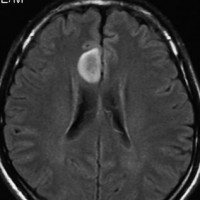

フレア画像です。左上前頭回の星細胞腫ですが,境界がとてもはっきりしていて限局性 localized single gyrus glioma です。びまん性 diffuseには見えません。IDH1の変異があり,1p/19qの欠失はないので星細胞腫グレード2です。上の例とは全く違う臨床像を示しますが,分子病理でも区別はつきません。頑張って早めに全摘出して治してしまった方がいいタイプです。再発を避けるために,supratotal resectionと言って,周囲の正常脳組織も10mmくらい余分に摘出します。